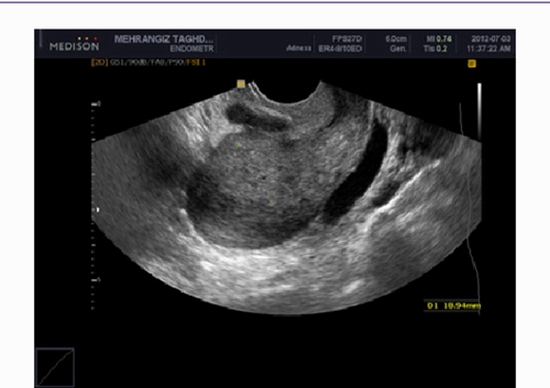

In this study we aimed to evaluate diagnostic accuracy of magnetic resonance imaging (MRI) and transvaginal sonography (TVS) in identifying the depth of myometrial invasion and cervical involvement and also their relationship with the uterine arteries resistance index (RI) and pulsatility index (PI) in endometrial carcinoma.

We performed a prospective study on 45 women with histologically confirmed diagnosis of endometrial carcinoma. The study was performed from October 2009 to December 2012. All the patients were evaluated by 3T MRI and TVS and transvaginal color Doppler sonography of uterine arteries. All the patients underwent hysterectomy and the result of imaging and pathologic studies were compared.

Mean age was 54.5 ± 10.8 years (33 to 77 years), mean gravid was 3.93 ± 2.8 and the mean parity was 3.9 ± 2.5. The pathology results indicated 29 patients (64.4%) in stage IA and 16 patients (35.6%) in stage IB. Mean endometrial thickness in stage IA patients was 18.4±14.4 mm and in stage IB patients was 38.5±11.5 mm. TVS also showed positive predictive value (PPV) of 76.5%, negative predictive value (NPV) of 88.9%, sensitivity of 81.3%, specificity of 85.7%, and accuracy of 84.1% for assessment of the depth of myometrial invasion in endometrial carcinoma. We found PPV of 86.7%, NPV of 92.3%, sensitivity of 86.7%, specificity of 92.3%, and accuracy of 90.2% for MRI study.

TVS can evaluate the depth of myometrial invasion with an acceptable accuracy when MRI is not available or cost-effective, or when MRI is contraindicated. Both preoperative MRI and TVS can predict low risk patients (less than 50% of myometrial invasion) accurately; thereby avoiding lymphadenectomy in these patients